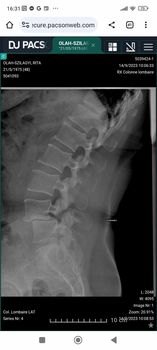

És délután fél 1-kor meglepetéssel érkezett a doktornő. Hozta a zárójelentésemet, a beutalókat a következő ellenőrzésekre, az előző nap készült felvételeket a gerincemről. Elmondta, hogy tényleg minden rendben van, mehetek haza! Azt se tudtam hirtelen kinek telefonáljak, hogy jöjjön értem, de rettenetesen boldog voltam. A férjem elindult haza a munkahelyéről, és 48 órával a műtétem után már úton voltam az otthonom felé.

Az eljárás neve: TLIF ágyéki gerincstabilizáció. Nem sérv, vagy porckorong műtét, hanem az instabil gerinc helyreállítása. Akkor van rá szükség, ha 2 csigolya kapcsolata nem teljesen stabil, ha csigolyacsúszás áll fenn. Ennek következtében az ágyéki csigolyák között a kapcsolatot biztosító porckorongok, kisízületek és a szalagrendszer meggyengülnek vagy károsodnak. Nekem az L4-L5-ös csigolyáim között már nem volt porckorong, egymáson ültek, így a gerinccsatorna, valamint a gyökcsatornák beszűkültek, nem volt átjárható "lyuk" közöttük, így az ideggyökök beszorultak, illetve a gerincvelő végéből származó rostoknál funkciózavar lépett fel. Továbbá az L4-es csigolya 1 cm-re elcsúszott a hasfalam felé.

A beavatkozás elvégezhető minimál invazív eljárással is, de engem felnyitottak 9-10 cm hosszan a hátamon, mert halmozott volt a probléma.

A csigolyák közötti hiányzó porckorong helyére egy távtartót ékeltek be, ami 8 mm-re felemelte a felső csigolyát. Ez nem a legoptimálisabb távolság, mert az egészséges csigolyáim között 12 mm a rés, de ennél többet nem lehetett emelni rajta.

Valamint az érintett csigolyákba hátulról csavarokat vezettek be, s ezeket rudakkal kötötték össze. A visszahúzás sem tökéletes, annyira csúszott a helyére az L4-es csigolyám, amennyire tudott. Szóval most 6 csavar tartja stabilan az ágyéki gerincem eldeformálódott részeit.